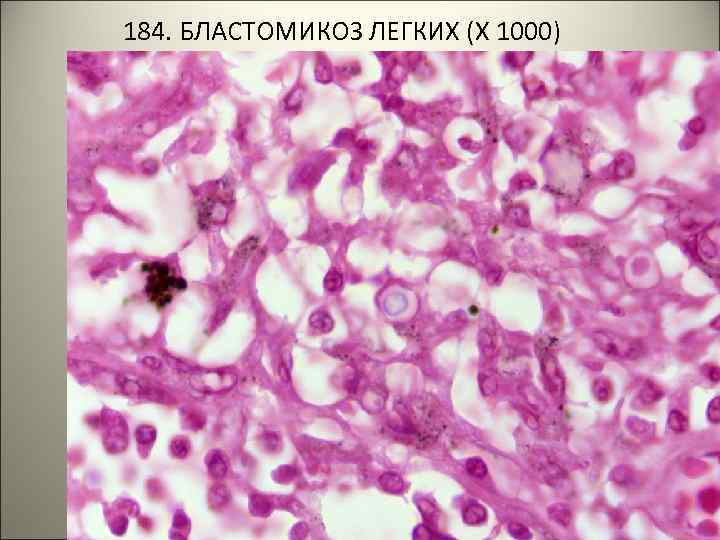

• 184. БЛАСТОМИКОЗ ЛЕГКИХ. • В ткани легкого очаги некроза и продуктивное воспаление с большим количеством гигантских клеток инородных тел, содержащих грибы черного цвета • УКАЗАТЬ НА РИСУНКЕ: • 1 – некроз • 2 – продуктивное воспаление • 3 – гигантские клетки • 4 – грибы.

184. БЛАСТОМИКОЗ ЛЕГКИХ (Х 50)

184. БЛАСТОМИКОЗ ЛЕГКИХ (Х 1000)